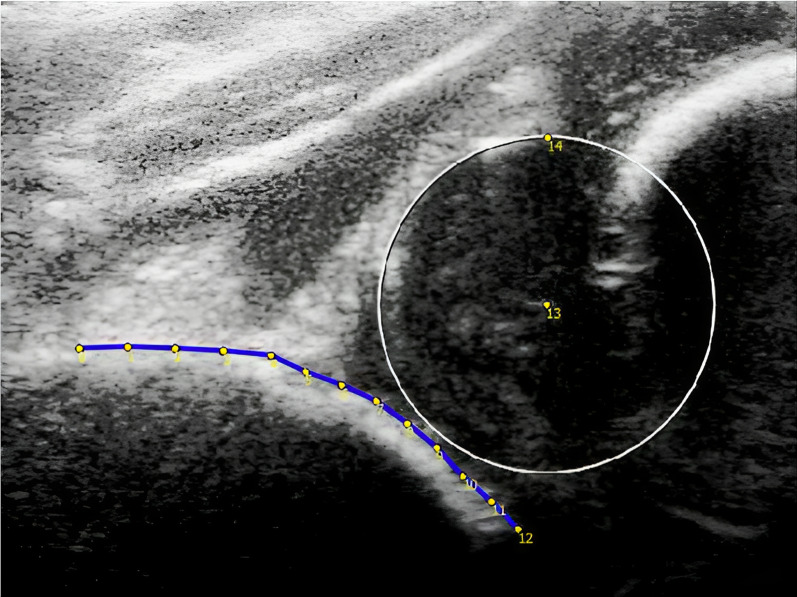

Background: Current methods to classify developmental dysplasia of the hip (DDH) on ultrasound (US) images, such as the Graf method, provide limited prognostic information. This study aimed to improve the prediction of the clinical course and outcome at age five of decentered hips, diagnosed on the first US made in the first months after birth, by identifying acetabular shape variants on these US images using a statistical shape model (SSM).

Patients and methods: US images of the hip were retrieved from a single-center retrospective cohort of patients with DDH Graf type D/III/IV. A SSM was created from the US images made at initial diagnosis.. The association between the identified acetabular shape variants and an unfavorable outcome (residual DDH at age five and open reduction and/or a pelvic osteotomy before age five) was established with multivariable regression models.